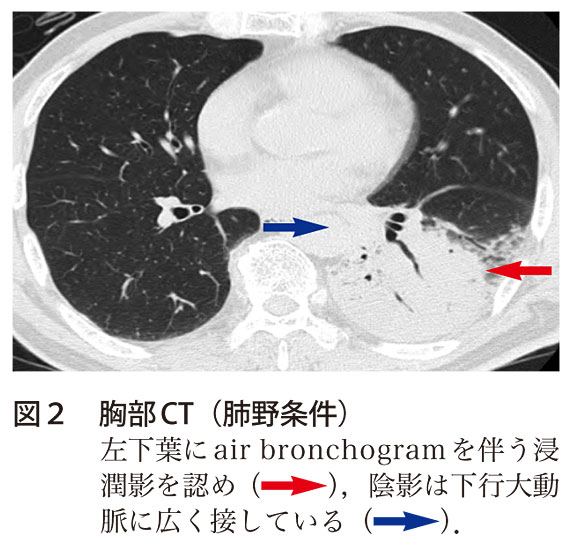

レジオネラ肺炎に伴う一過性の脳病変 実践 画像診断q A 羊土社 レジデントノート 羊土社